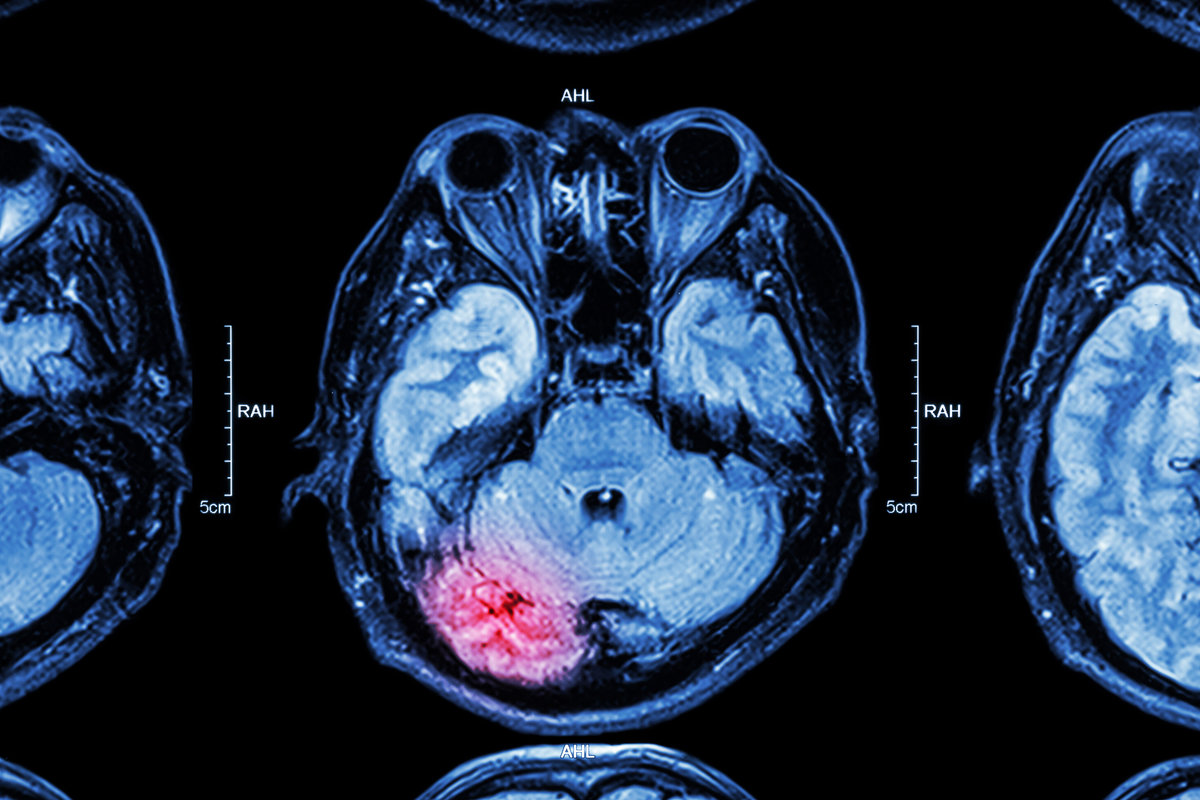

A traumatic brain injury, or TBI, occurs when a sudden blow, jolt, or penetrating wound disrupts normal brain function. The severity ranges from mild concussions to severe injuries involving prolonged unconsciousness, permanent cognitive impairment, and death. According to the Centers for Disease Control and Prevention (CDC), there were over 69,000 TBI-related deaths in the United States in 2021, representing approximately 190 deaths every day. These numbers do not capture the far larger population of survivors living with lasting disabilities.